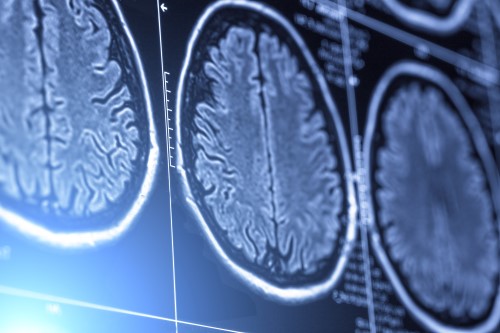

The Arthur and Sonia Labatt Brain Tumour Research Centre (BTRC) is where top scientists and clinicians from The Hospital for Sick Children (SickKids) and the University Health Network (UHN) collaborate on human brain tumour studies.

The BTRC aims to cure children and adults with brain tumours, while progressing towards more predictable clinical control of the condition. By determining how brain tumours form on a molecular level, our team is in a unique position to develop new scientific and clinical therapies.

- Investigate the molecular basis of brain tumour progression through an analysis of genes which controls the cell cycle, signal transduction pathways, tumour angiogenesis, and invasion.

- Study the role of cell death (apoptotic) and tumour suppressor gene pathways in human brain tumours.

- Develop new methods to treat patients based on our growing knowledge of human brain tumours. Discoveries from the laboratory are quickly translated to effective clinical trials for patients with intracranial neoplasms.